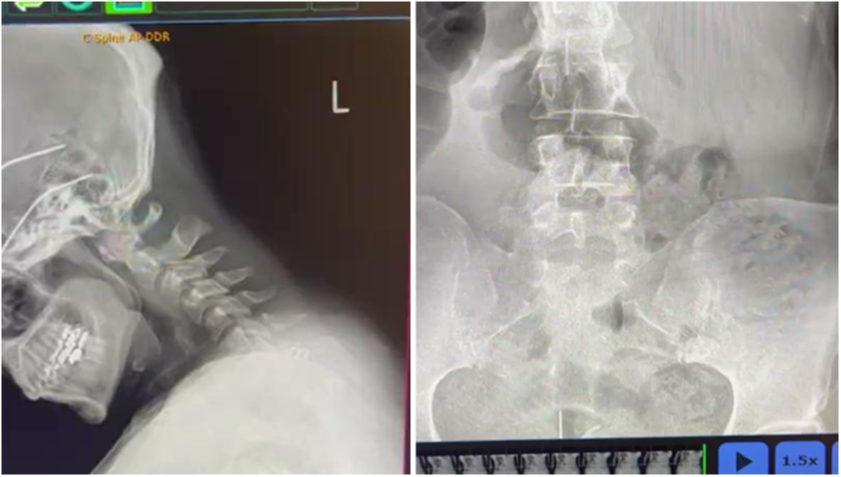

1. PULSE X-RAY DIGITAL MOTION

You'll be introduced to the tool that has revolutionized chiropractic care. These "moving" x-rays have a 93% inner Doctor reliability score making it the most accurate spinal analysis to date.

Pulse X-Ray's remove the guesswork from your practice. By integrating this technology, you’ll drastically enhance the quality of your care, achieving far better patient outcomes in significantly less time.

This transformative approach ensures you’re not just treating but truly optimizing spinal health with confidence and precision, setting a new standard in patient care.